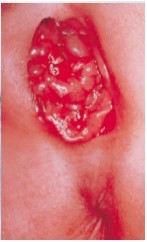

6 weeks to 6 months after chancre: Can lead to systemic symptoms, lesions (condyloma lata- shown below) which are highly infectious.

Treponema pallidum (syphillis): initial lesion occurs at site of contact and is painless (chancre), causing vulvar, regional lymphadenopathy (3 weeks post-contact).